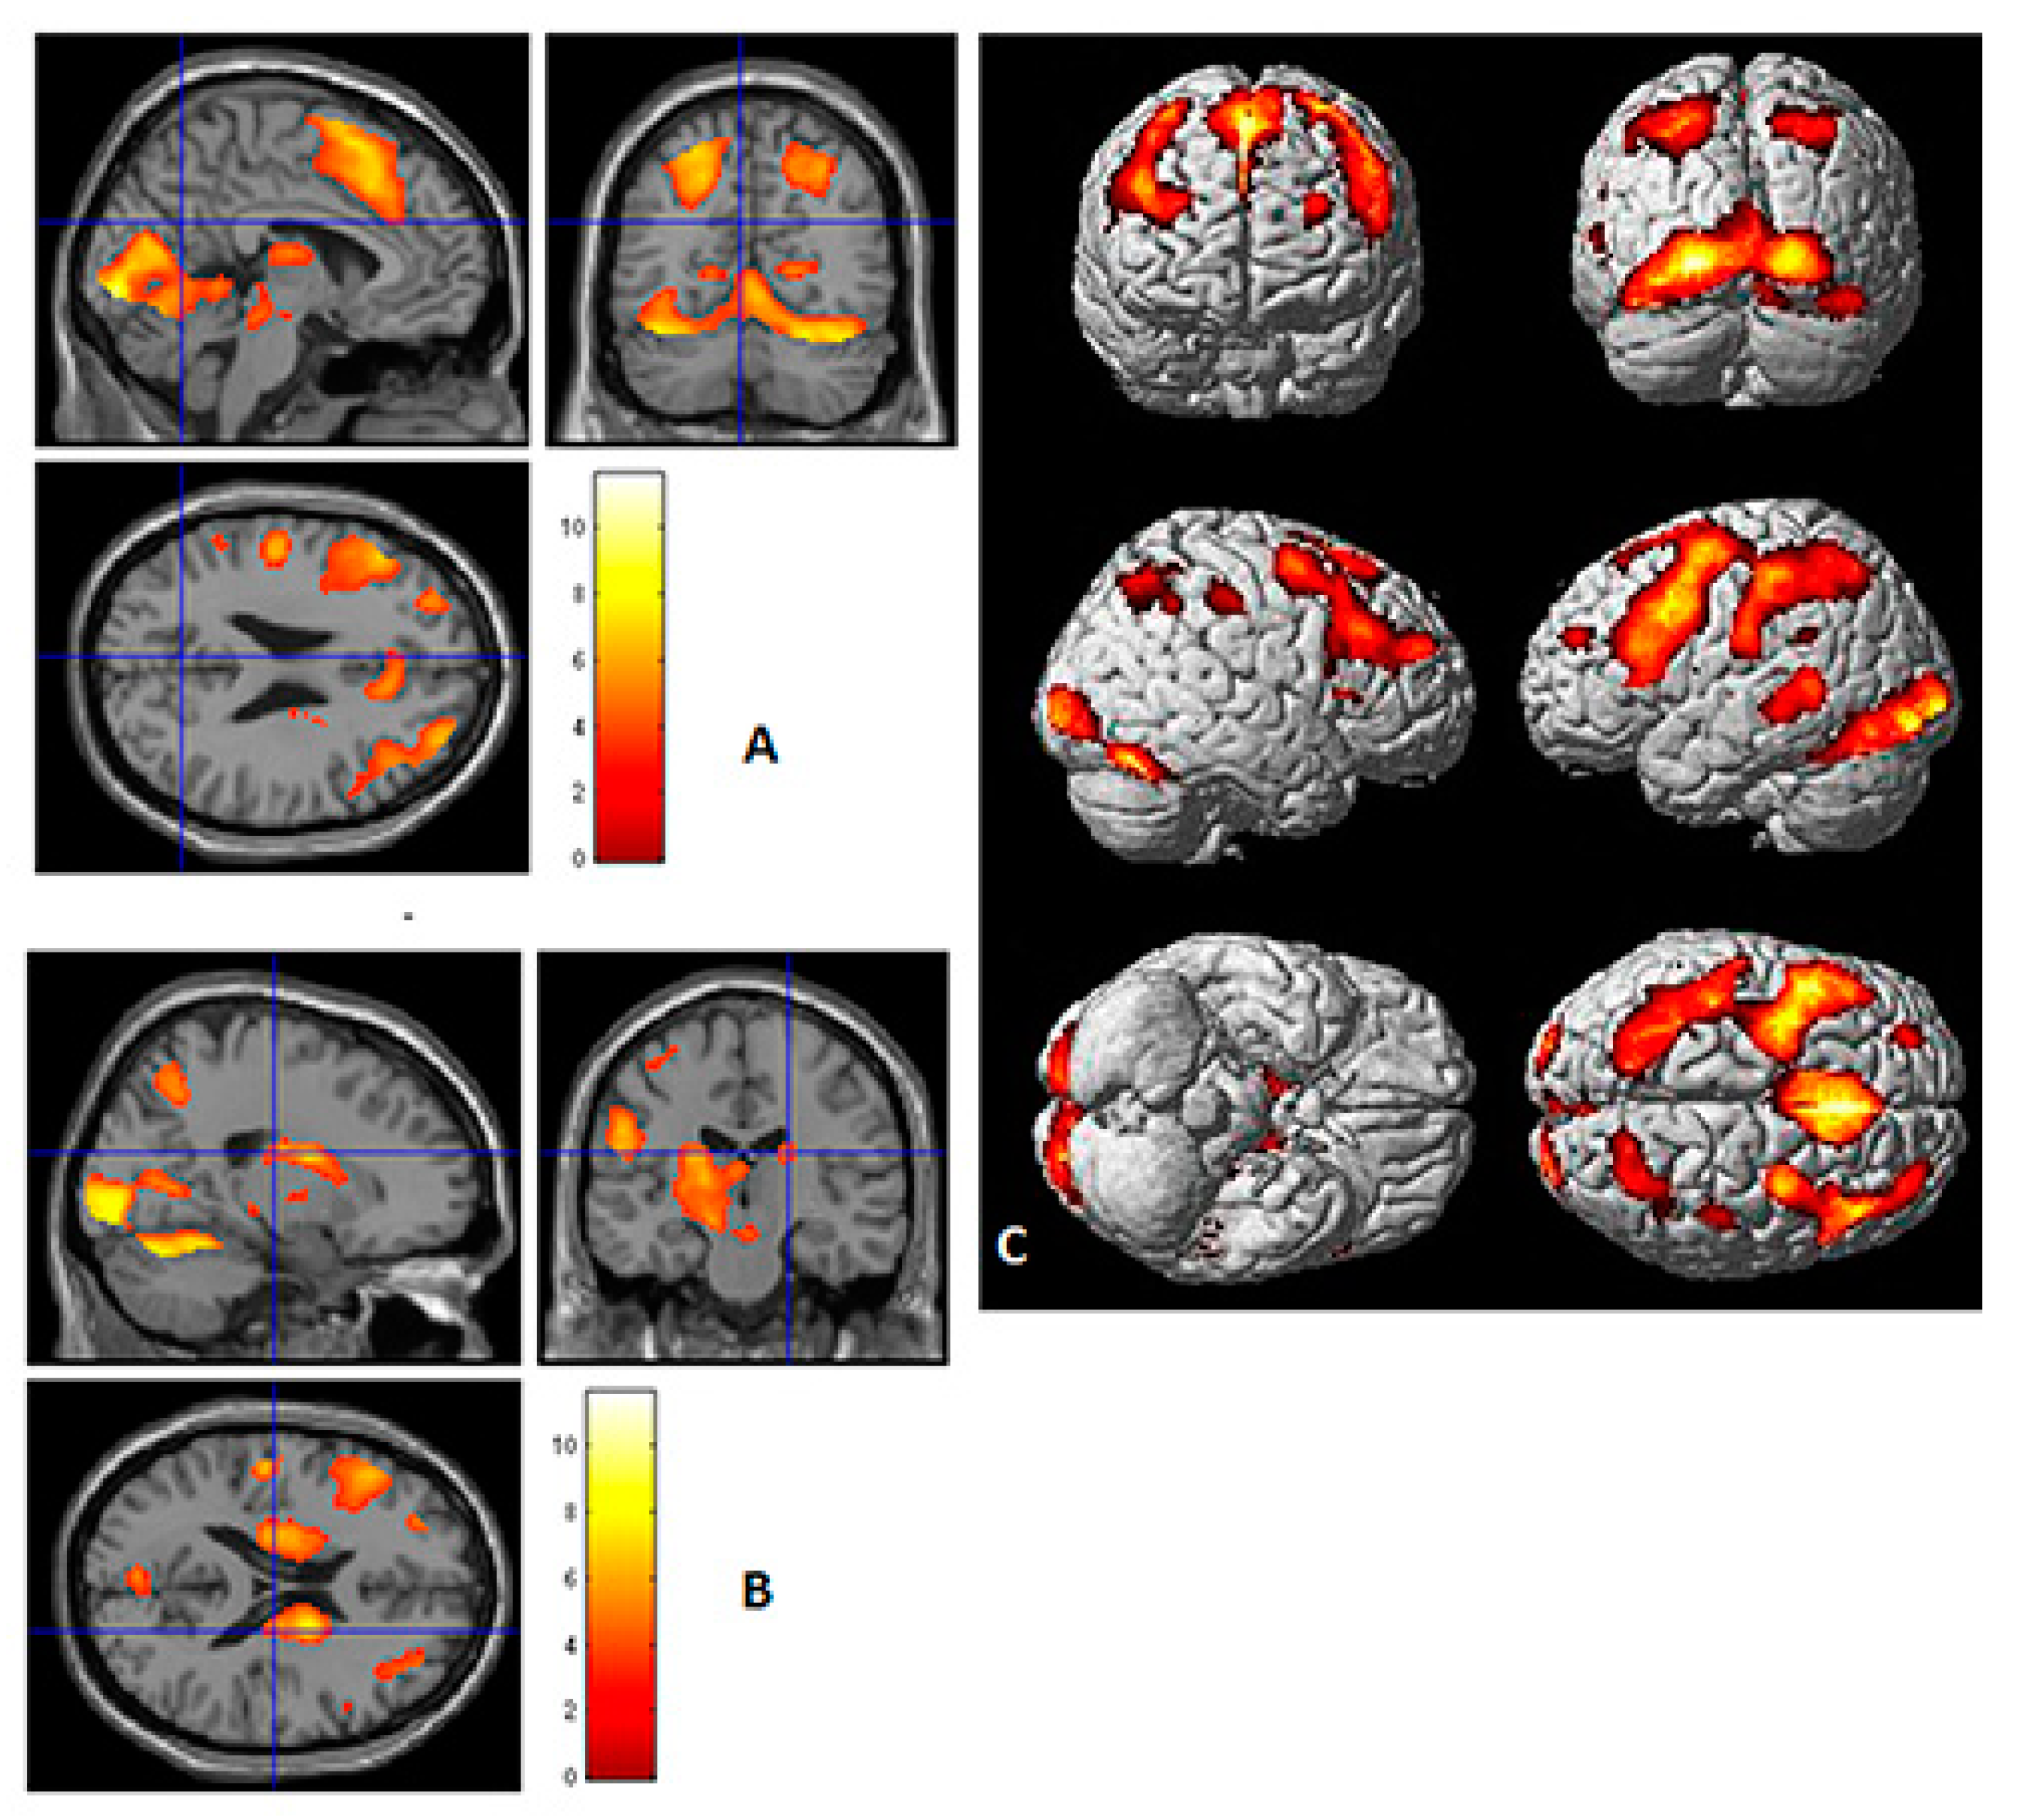

3.1. Personality Orientations and fMRI Activity

3.2. Emotion/Feeling-Action Personality Orientation

3.3. Intuitive/Imaginative Personality Orientation

3.4. Logical/Thinking Personality Orientation

3.5. Material/Pragmatic Personality Orientation